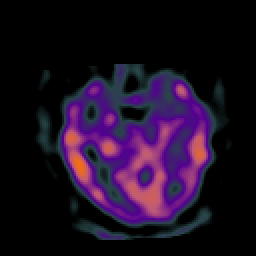

Subacute Stroke, overlay -- Slice #9

[Home][Help][Clinical] Slice 9